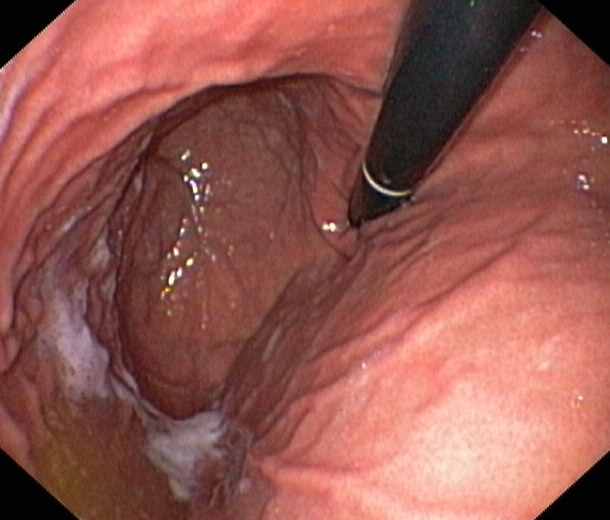

A Normal Gastric Fundus

A normal gastric fundus. Just click on a picture!

Diverticulum in the gastric fundus